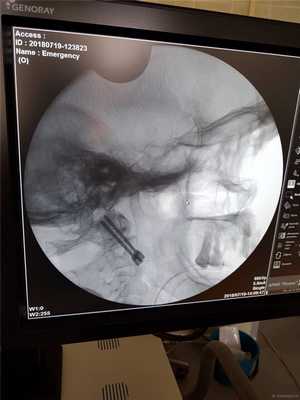

Вкручивается второй винт.

На контрольной КТ стояние винтов хорошее без промаха.